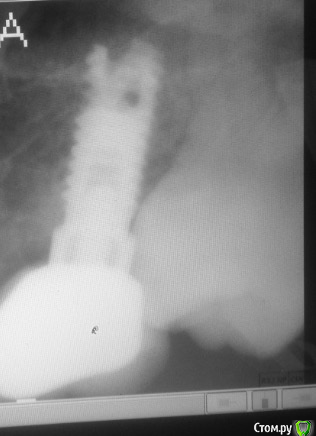

Вот старый снимок, лучше видно как залечен зуб и свежее фото, сохраняется отёк, болит если надавливать.

На снимках кармана не видно, нужен очный осмотр и зондирование десневой борозды, как альтернатива проведение компьютерной томографии.